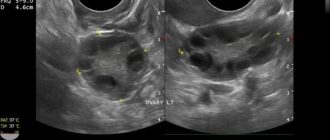

Основные признаки мультифолликулярных яичников (МФЯ) – информация для пациентов — клиника «Добробут» Мультифолликулярные яичники

Мультифолликулярные яичники и беременность — можно ли забеременеть? Мультифолликулярные яичники и многоплодная беременность Функциональность

Мультифолликулярные или поликистозные яичники Мультифолликулярными яичниками называют такие яичники, у которых одновременно увеличено несколько